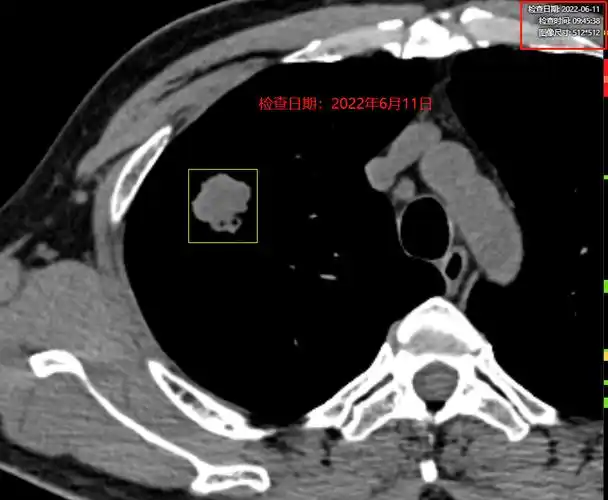

家属提供的ct检查报告单.

巫医生阅片以后,发现这个结节是一个典型的周围型肺癌.